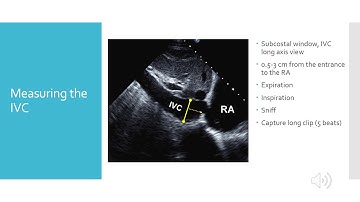

Estimation of RVSP